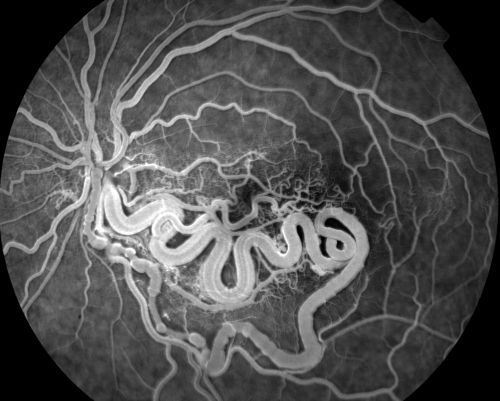

Wyburn Mason Syndrome

28 year old female, visual acuity OS 20/200